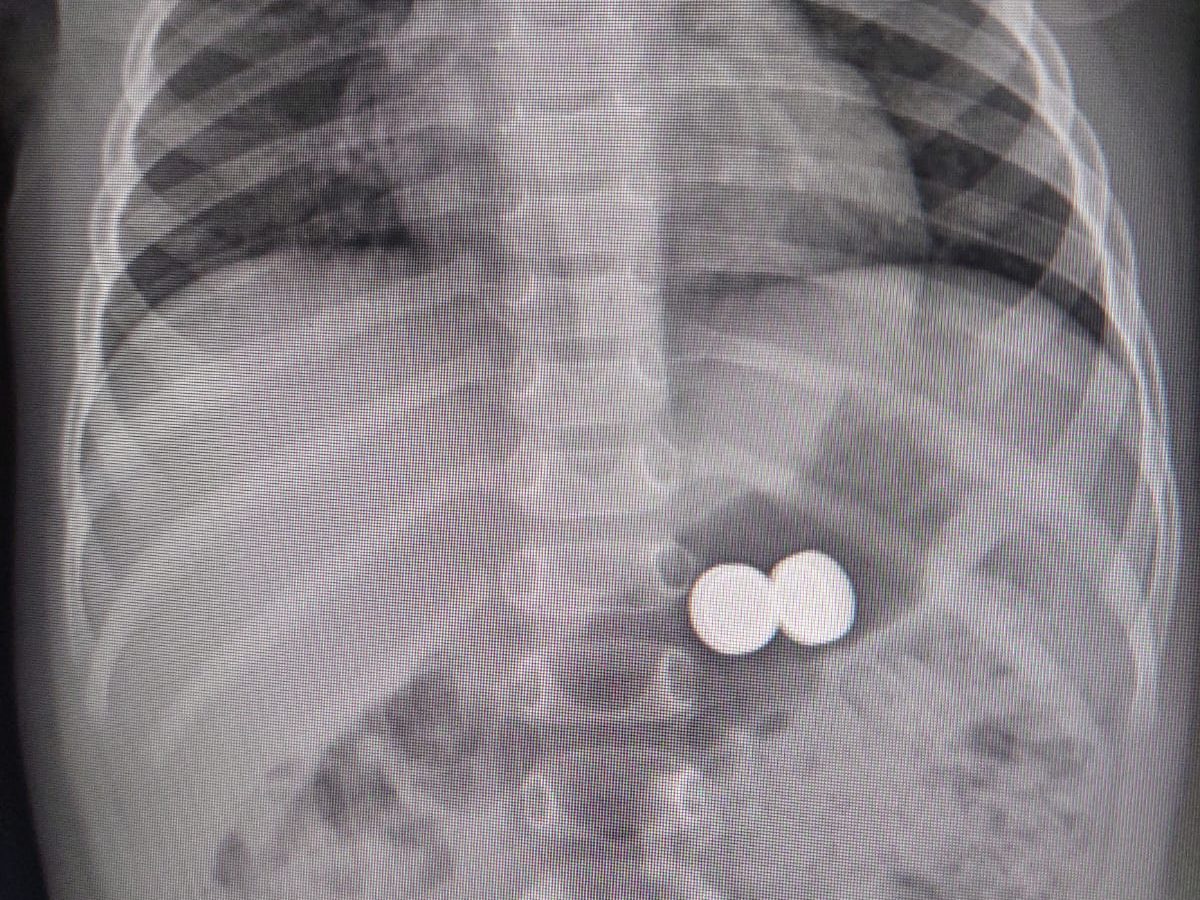

Una bambina di un anno è stata condotta d’urgenza all’ospedale Garibaldi-Nesima, dopo aver ingerito due batterie a bottone. Il pronto intervento dei medici ha permesso di rimuovere i corpi estranei senza conseguenze gravi.

L’incidente è stato segnalato dai genitori della piccola, che hanno prontamente trasportato la bambina all’ospedale di Acireale. A seguito della segnalazione, è stato immediatamente contattato il Pronto Soccorso Pediatrico del presidio ospedaliero Garibaldi-Nesima, dove la dott.ssa Rita Leocata e la dott.ssa Valeria Di Stefano hanno immediatamente dato disponibilità per accogliere la piccola e procedere alla rimozione delle batterie.

Una volta arrivata al Pronto Soccorso Pediatrico, è stato prontamente allertato il gastroenterologo, dott. Domenico Catarella, insieme agli anestesisti della sala operatoria, dott. Giuseppe Calabrese e dott.ssa Lucia Terranova. Grazie alla loro tempestiva collaborazione, si è proceduto con successo alla sedazione e rimozione dei corpi estranei.

Al momento, la bambina si trova sotto osservazione presso lo stesso Pronto Soccorso Pediatrico e verrà monitorata per alcune ore. Le condizioni della piccola sono stabili e non sono emerse complicazioni.